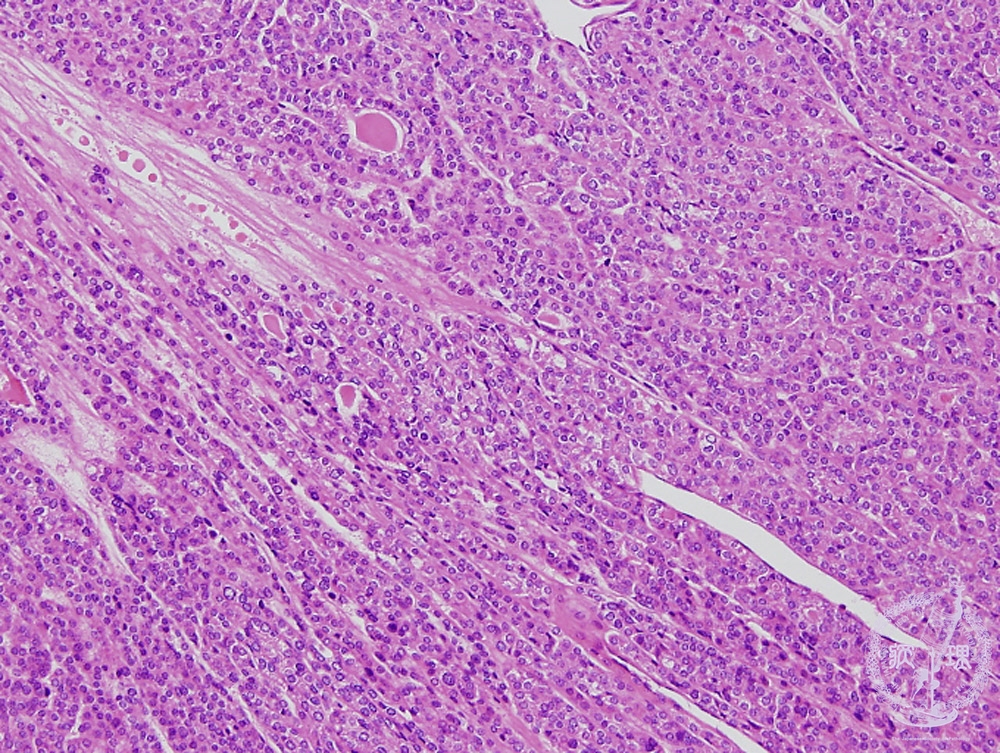

Microscopic findings (HE stain, middle power view). The tumor cells are arranged in follicular or trabecular architecture. The nuclei of tumor cells are round and small.